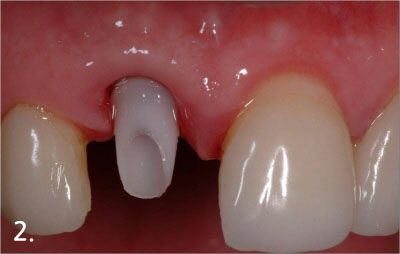

Immediate Implant Placement

Placing implant right after extraction

Connecting abutment

Cementation of implant crown to begin function